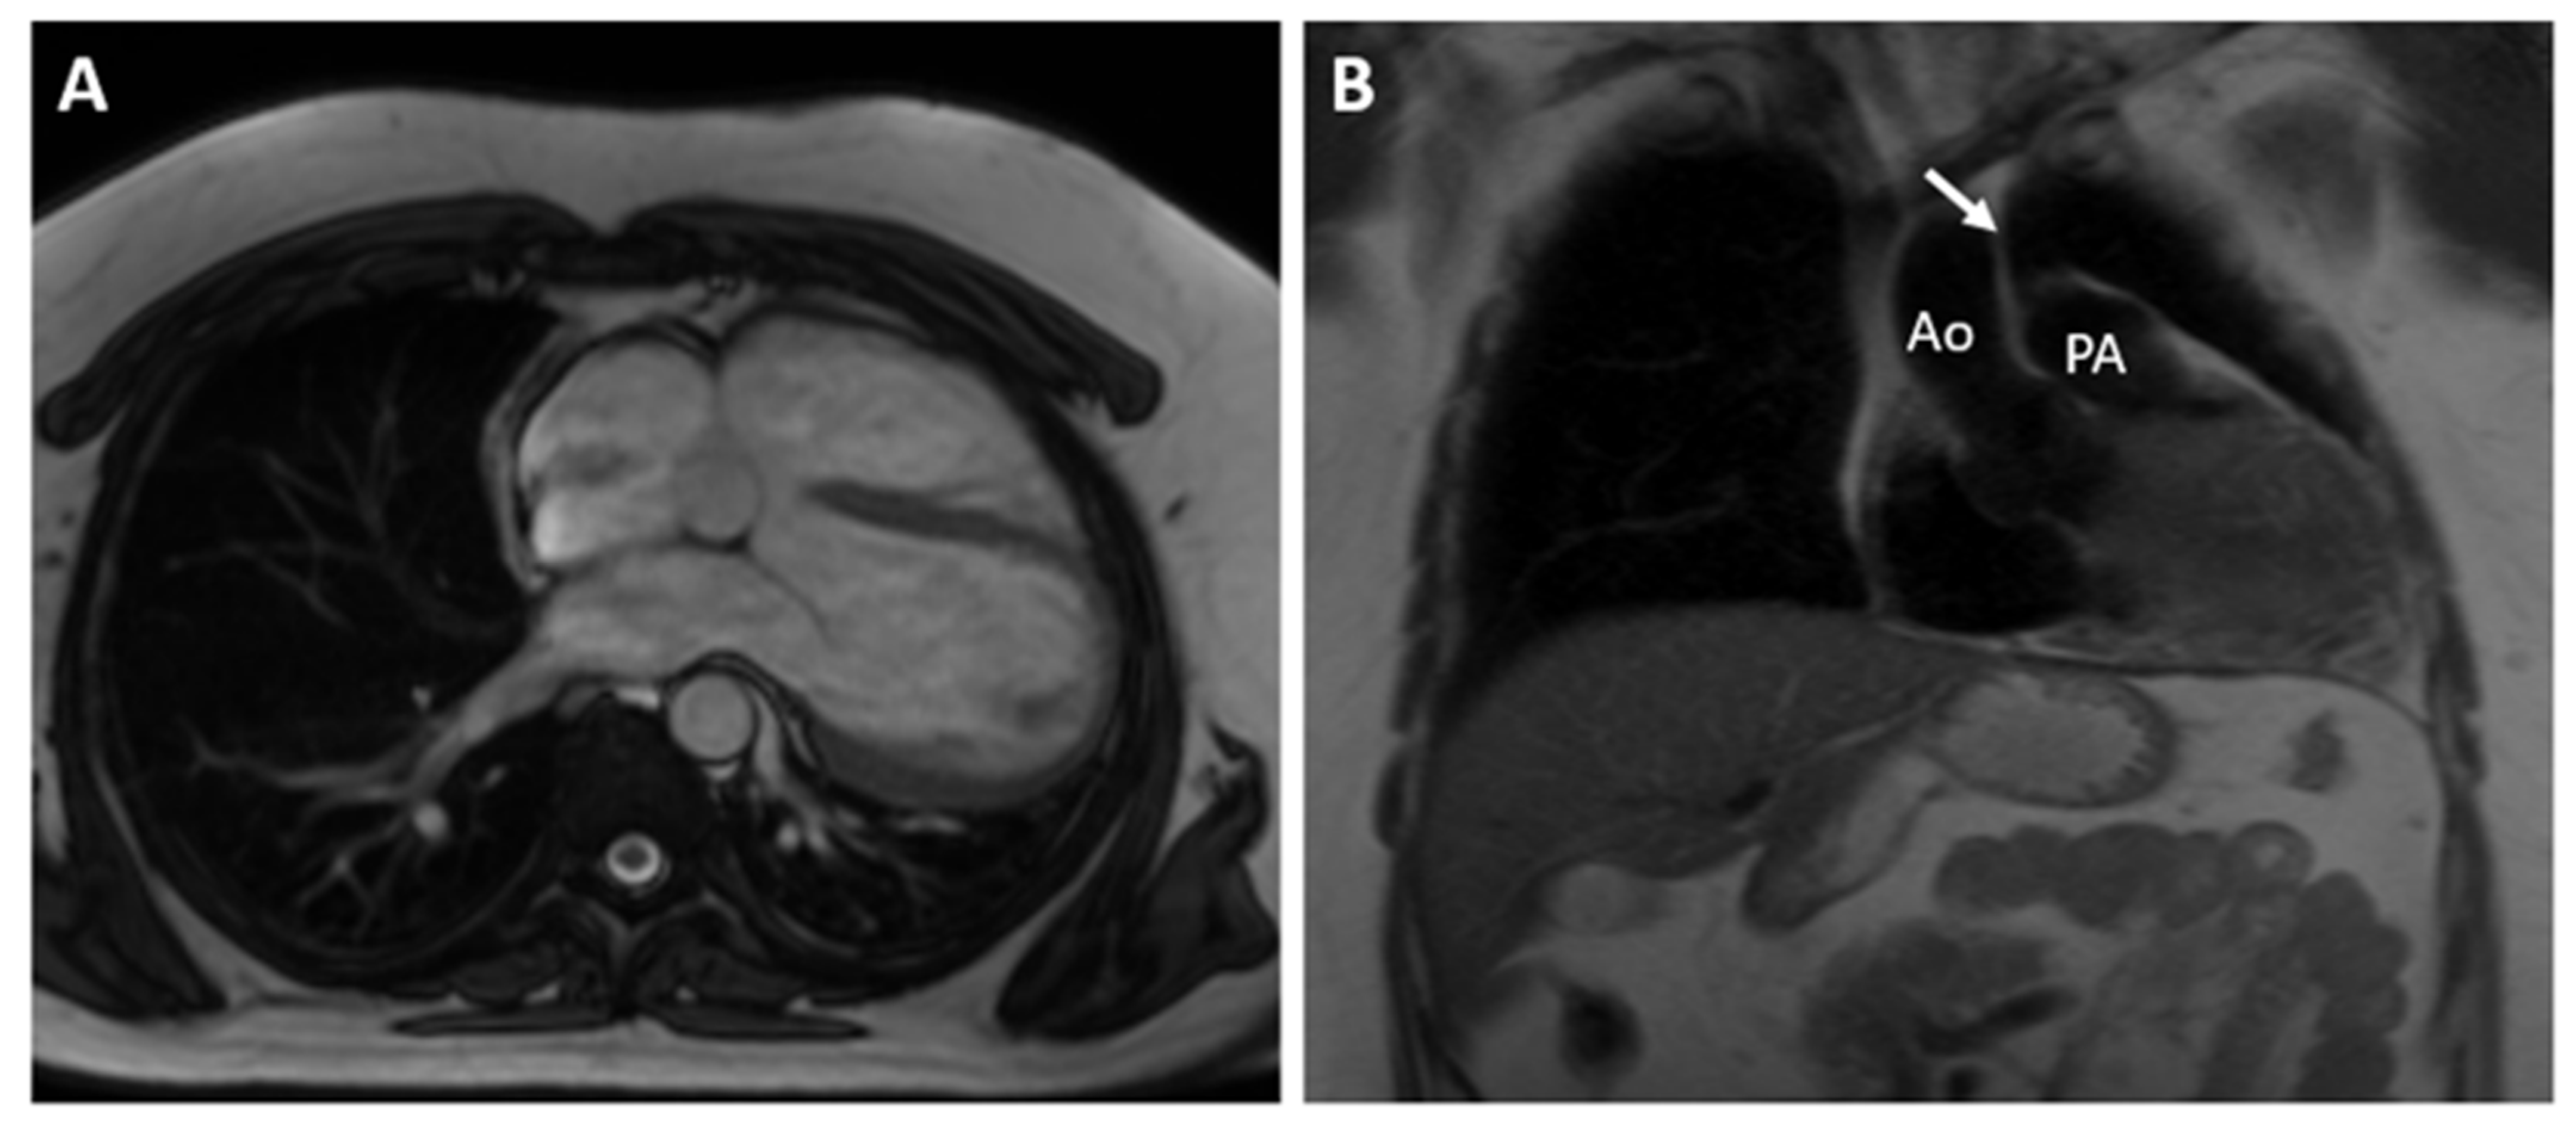

A 36-year-old male with first grade essential arterial hypertension with good medical control was referred for routine cardiovascular exam. He had a medical history of heart murmur since childhood and has been told to have interventricular communication. No prior medical records were submitted. Physical examination did not demonstrate any cardio-pulmonary abnormalities. An electrocardiogram (ECG) revealed sinus rhythm at 62 bpm, normal axis, poor R-wave progression in the precordial leads and repolarization abnormalities and negative T waves in V1–V4 (Figure 1).

Figure 1. ECG of the patient.

In patients with CAP, the history and physical examination are often nonspecific and with no role in making the diagnosis. The ECG is usually normal in small or partial defects. In cases with complete pericardial absence, some typical findings include right axis deviation, complete or incomplete right bundle block and sinus bradycardia induced by vagal stimulation [7]. In these cases, chronic lung disease, congenital interventricular and interatrial septal defects with hemodynamically significant shunts should be considered. Echocardiography is also not characteristic, but some findings may raise the clinical suspicion of this diagnosis. They include unusual acoustic windows due to the abnormal heart position, right ventricle dilatation, cardiac hypermobility, “teardrop” appearance, and paradoxical motion of the interventricular septum [8]. In our case, a dilated right ventricle was registered at TTE, and in the presence of atrial septal defect (ASD), we referred the patient for CMR. Our differential diagnosis was for a significant left–right shunt. Chest X-ray finding in complete pericardial absence is known as “Snoopy sign” and include combination of levoposition of the heart, elongation and flattening of the left heart border, radiolucency between the pulmonary artery and aorta due to interposition of lung tissue and loss of the right heart border [7]. In the past, a diagnostic left pneumothorax has been used to confirm the diagnosis showing pneumopericardium [9]. Nowadays, the imaging modalities of choice for detecting pericardial absence are computed tomography and cardiac magnetic resonance. Since they are not affected by the acoustic window, they have a better sensitivity in identifying the levoposition of the heart and lung interposition in the aorto-pulmonary window and between the inferior cardiac border and the diaphragm. CMR is the gold standard for evaluating the cardiac anatomy, volumes and function and can demonstrate any functional abnormalities or regional bulging and herniation of the heart associated with pericardial agenesis. CT, on the other hand, has a greater spatial resolution and can be of help in identifying small defects [10,11].